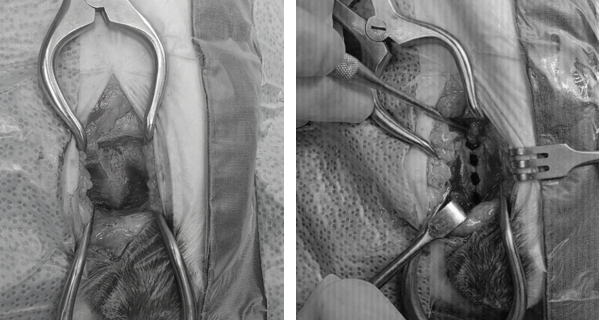

루키의 실제 수술 전 후 사진

골반의 치골을 노출시킨 후 전기 소락기를 이용하여 성장판의 절반정도를 손상시킵니다. 위 사진 오른쪽에서 보이는 4개의 구멍이 손상시킨 성장판 부위입니다. 수술은 1시간만에 종료되었습니다.